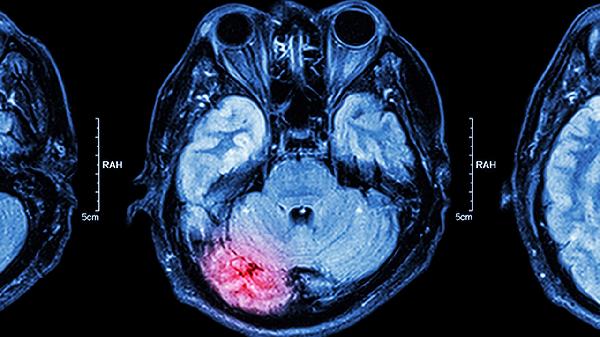

颅脑损伤后3-6个月恢复期内,药物能促进受损脑细胞修复。但伴有颅内高压或出血倾向者禁用。需在神经外科医生指导下使用,定期复查头颅CT评估恢复情况。